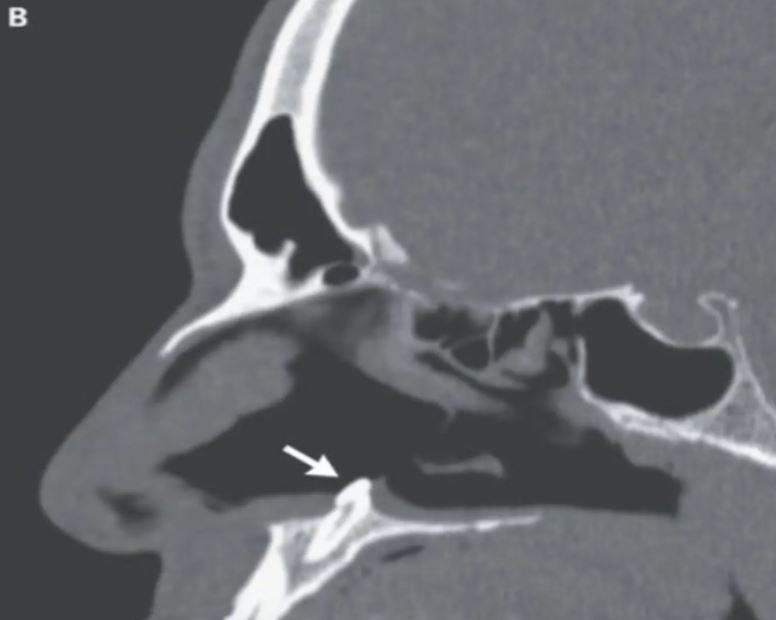

Pemeriksaan lanjut mendapati, terdapat lubang sepanjang 2 sentimeter pada bahagian belakang septum.

Doktor yang menjalankan pemeriksaan seterusnya mengesan jisim putih yang keras pada lubang hidung sebelah kanan, dan disahkan batang gigi ektopik terbalik.